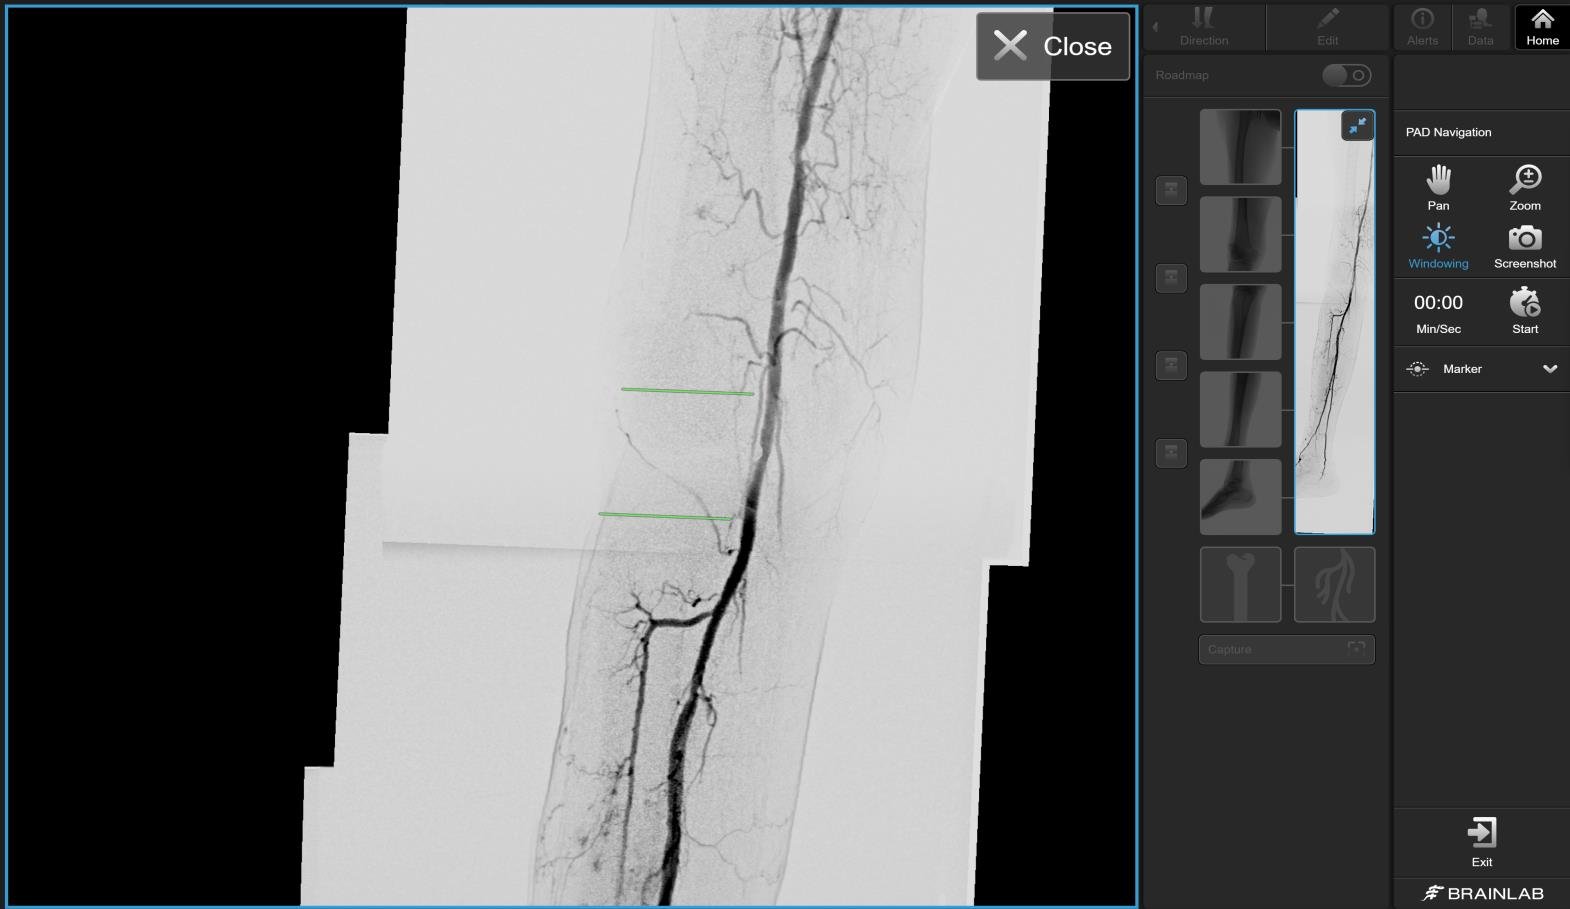

The software combines previously acquired angiography images into one continuous visualization of the vessels. This roadmap is displayed live as an overlay during the procedure, ensuring that the physician always has a complete overview. The system easily connects to mobile C-arms and integrates directly with PACS for image storage.

• Reusable roadmap that adapts in real time during the procedure

• Full overview of the lower limbs and iliac arteries in a single image

• Automatic image merging for a continuous vascular view